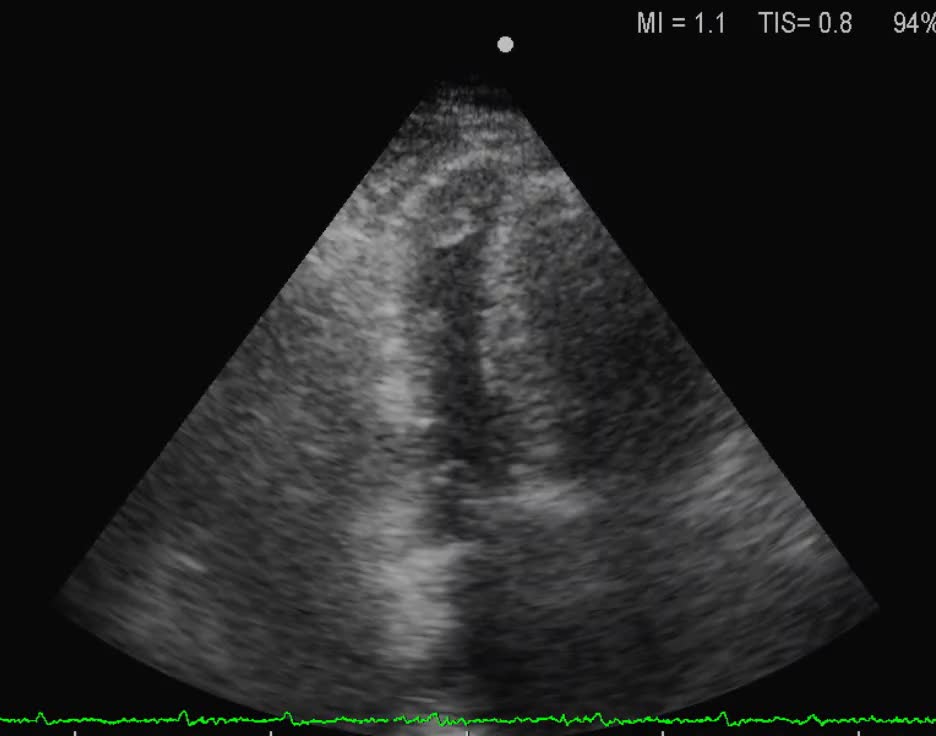

Titolo:

Cardiomiopatia restrittiva

Autore:

Andrea Barbieri